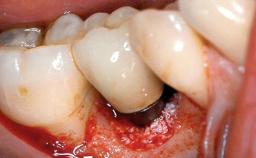

Excess Cement Resulting in Peri-implant Infection Presenting as a Draining Sinus Tract

Biological complications caused by undetected cement residue have been receiving much attention. Excess cement might be responsible not only for rapidly developing of peri-implantitis, but also for delayed or chronic manifestations of the disease many years after cementation (Wilson 2009; Linkevicius and coworkers 2013). Invitro and clinical studies have shown that it is very difficult or even impossible to completely clean up excess cement at subgingival margins, so popular in cemented restorations (Agar and coworkers 1997; Linkevicius and coworkers 2011, 2012). Possible outcomes of biological complications due to excess cement range from temporary inflammation of the peri-implant soft tissues without any serious esthetic and functional consequences all the way to implant loss. This report describes a case of peri-implantitis caused by residual cement; as well as the management and quite unusual resolution of the complication. The patient presented in 2009 with a draining sinus tract, tenderness on chewing, and tissue contact above the implant-supported restoration. The implant had been restored approximately three years before.